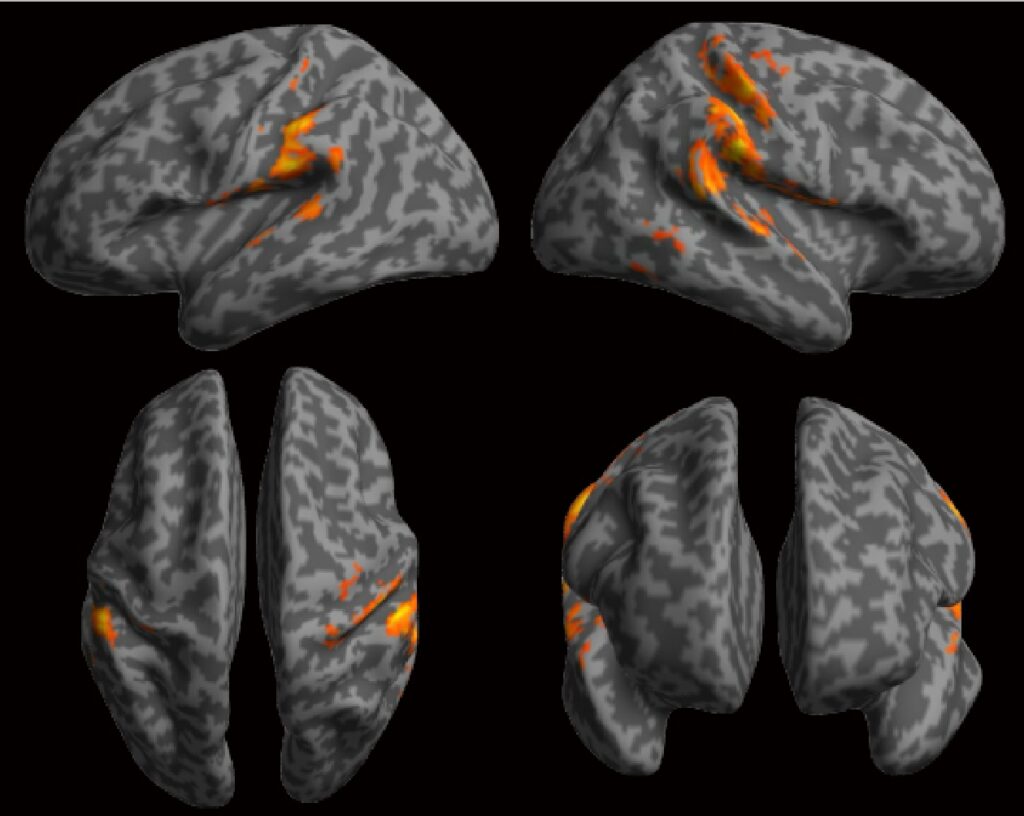

非侵襲的脳活動計測

本講座では、さまざまな脳疾患を対象とした非侵襲的脳計測手法を実施しています。これらの手法は、患者様に身体的な負担をかけずに、脳構造や活動の計測ができることが特徴です。てんかんモニタリングの一環として、頭皮脳波計測を行っており、てんかん発作時の脳波を解析し、てんかん発作のメカニズムの解明や最適な治療方針の策定に役立てています。また、臨床研究や医師主導の治験においては、本学の放射線科学講座、小児科学講座、神経内科学講座と協力し、機能的磁気共鳴画像法(fMRI)やポジトロン断層撮影(PET)を活用して、脳の特定領域の活動を可視化し、認知機能や脳疾患のメカニズム解明に取り組んでいます。